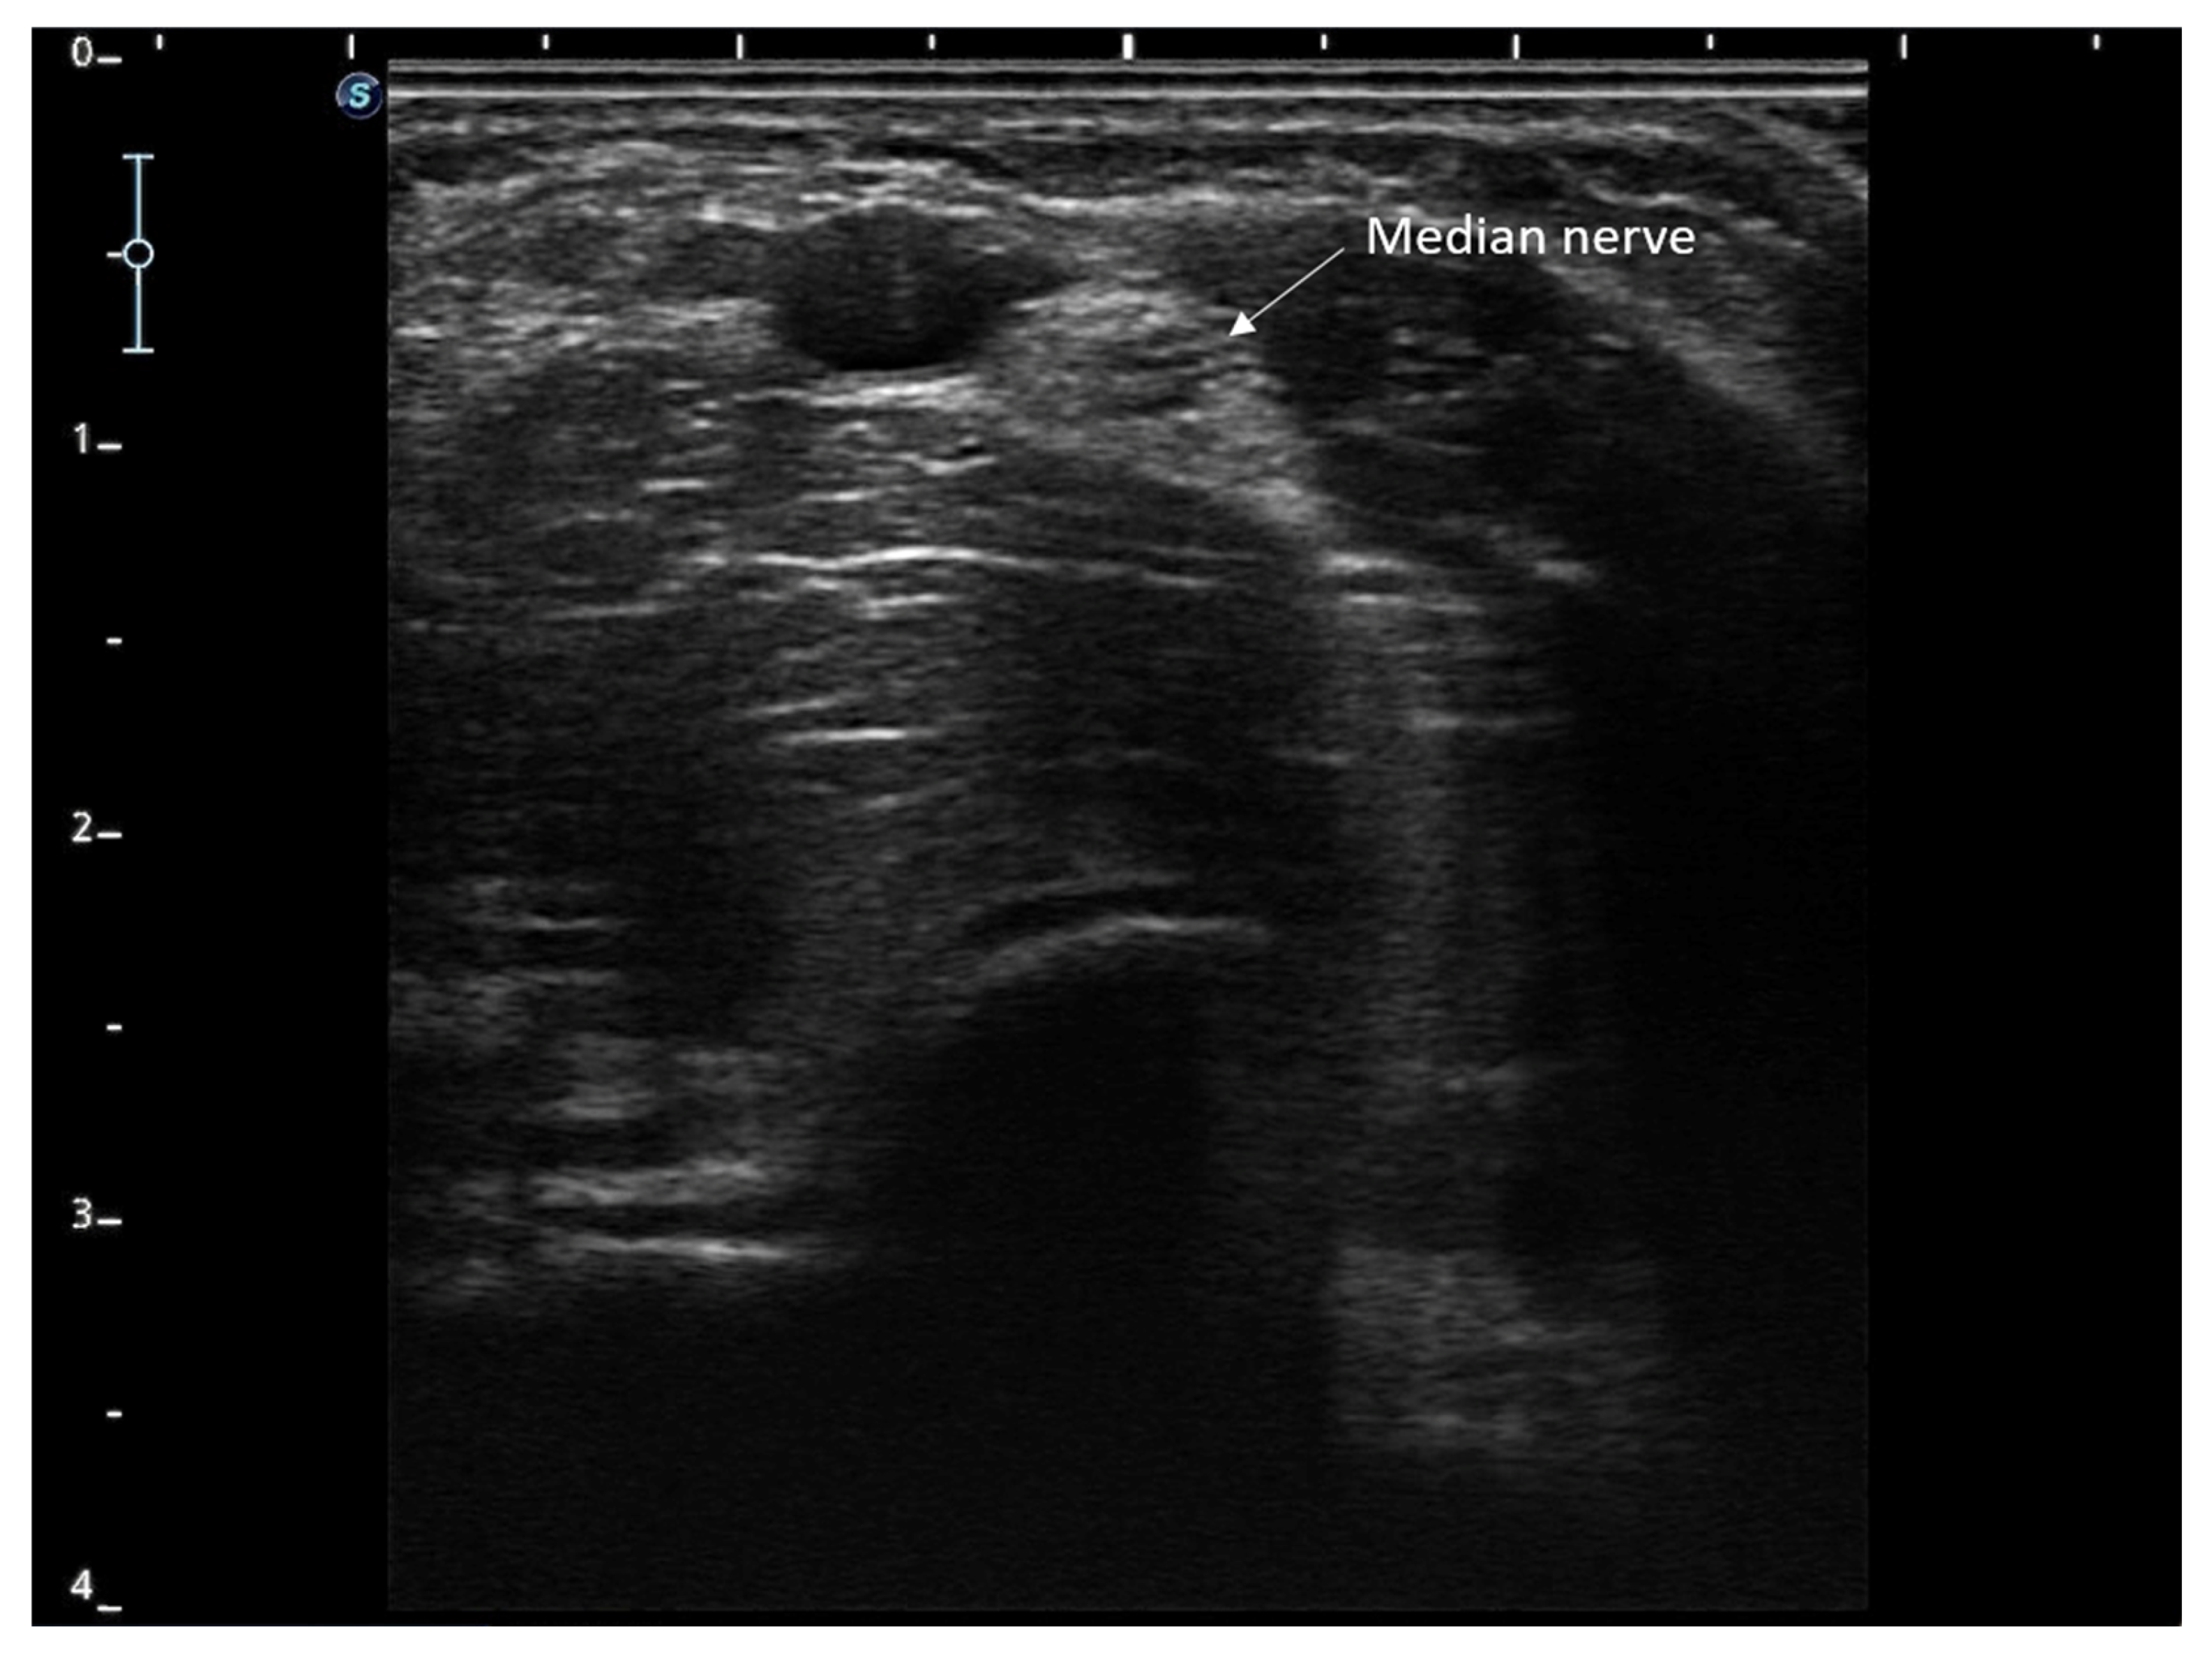

- Li, R.; Lu, J.; Wang, M.; Zhang, P.; Fang, H.; Yang, K.; Wang, L.; Zhuang, J.; Tian, Z.; Yang, J.; et al. Ultrasound-Guided Median Nerve Electrical Stimulation to Promote Upper Limb Function Recovery after Stroke. Evid. Based Complement. Altern. Med. 2022, 2022, 3590057. [Google Scholar] [CrossRef]

- Chu, X.L.; Song, X.Z.; Li, Y.R.; Wu, Z.R.; Li, Q.; Li, Q.W.; Gu, X.S.; Ming, D. An ultrasound-guided percutaneous electrical nerve stimulation regimen devised using finite element modeling promotes functional recovery after median nerve transection. Neural Regen. Res. 2022, 18, 683–688. [Google Scholar] [CrossRef] [PubMed]